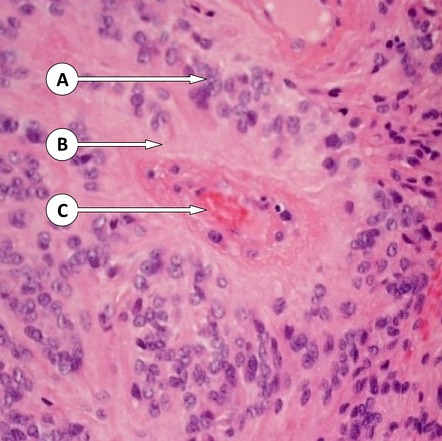

Микрофотографии гистологии глиобластомы головного мозга